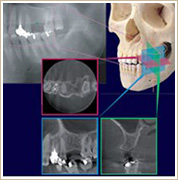

下顎に埋伏した親知らず

2次元の平面なレントゲン写真です。

左下の親不知の歯が横向きになった状態で下顎の中に埋まっています。

矢印は大きな神経や血管の入っている下歯槽管という部分です。

この親不知の抜歯手術で、近接した下歯槽管を傷つける危険性があります。

この写真のみでは、手術前の情報が不足しています。安全性を高めるためにCT診査を行いました。

横から見ているスライス像の1枚です。

正面から見ているスライス像の1枚です。

上下方向から見ているスライス画像の1枚です。

CTのデータを基に3Dイメージで表示した画像です。

ここには代表的な3方向からのデータのみを掲載しましたが、3次元のあらゆる方向から多数のスライスした画像を見る事が出来ます。